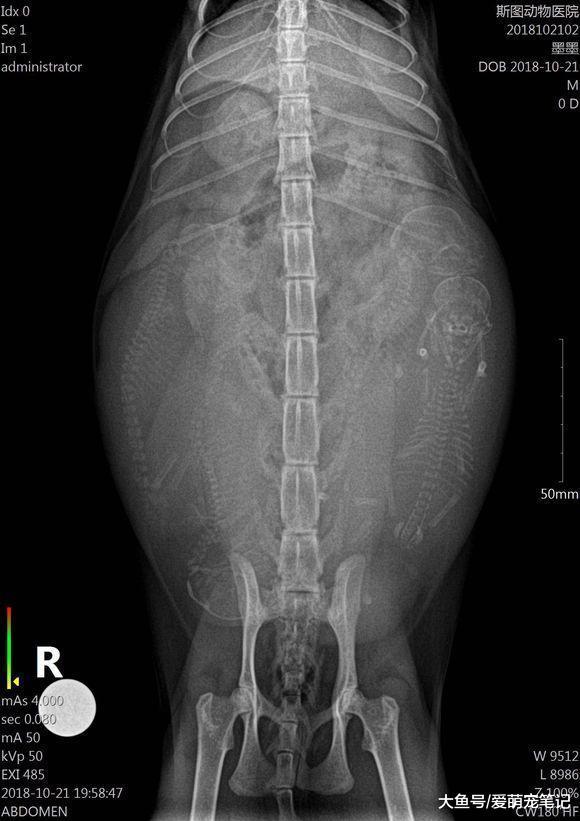

带家里的狸花猫去做产检, 意外收获四只小生命, 网友: 喜当猫外婆